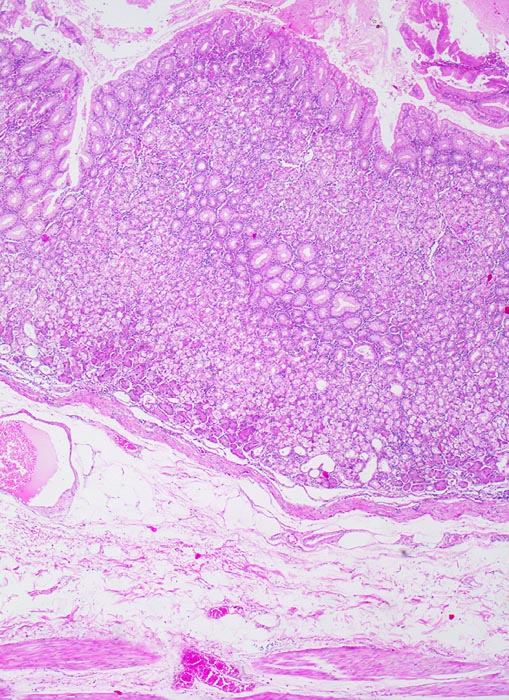

normaler Magenkorpus

Magenkorpus

Die kurzen Foveolae gastricae erscheinen teilweise wegen schrägem Anschnitt der Mukosa in die Tiefe verlagert. Unter der Mukosa folgt eine schmale Lamina muscularis mucosae und daran anschliessend das lockere Bindegewebe der Submukosa. Am unteren Bildrand ist die innere Schicht der Muscularis Propria erkennbar.